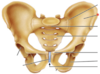

8

Q

A

Glenohumeral Joint

9

Q

A

Scapula

10

Q

A